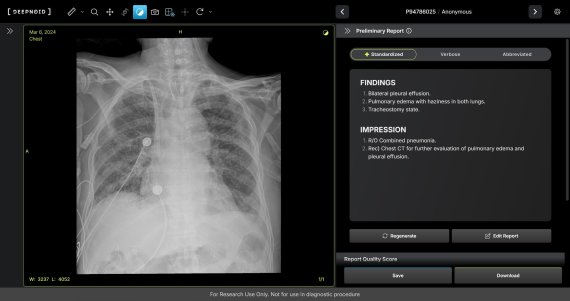

M4CXR 판독 예시 이미지. 딥노이드 제공.

M4CXR은 흉부 X-ray 영상에서 41종의 병변을 판독해 수초 만에 일관성 있고 신뢰성 높은 판독소견서 초안을 작성한다. 이는 흉부 X-ray 영상과 대응되는 1,000만 건 이상의 판독소견서 데이터를 학습해 구현된 기술로, 특히 응급상황에서 의료진이 즉시 예비 판독 결과를 받을 수 있어 중요한 임상 결정과 환자 진료에 더욱 집중할 수 있도록 지원하며 영상의학과 전문의의 판독을 보조한다.